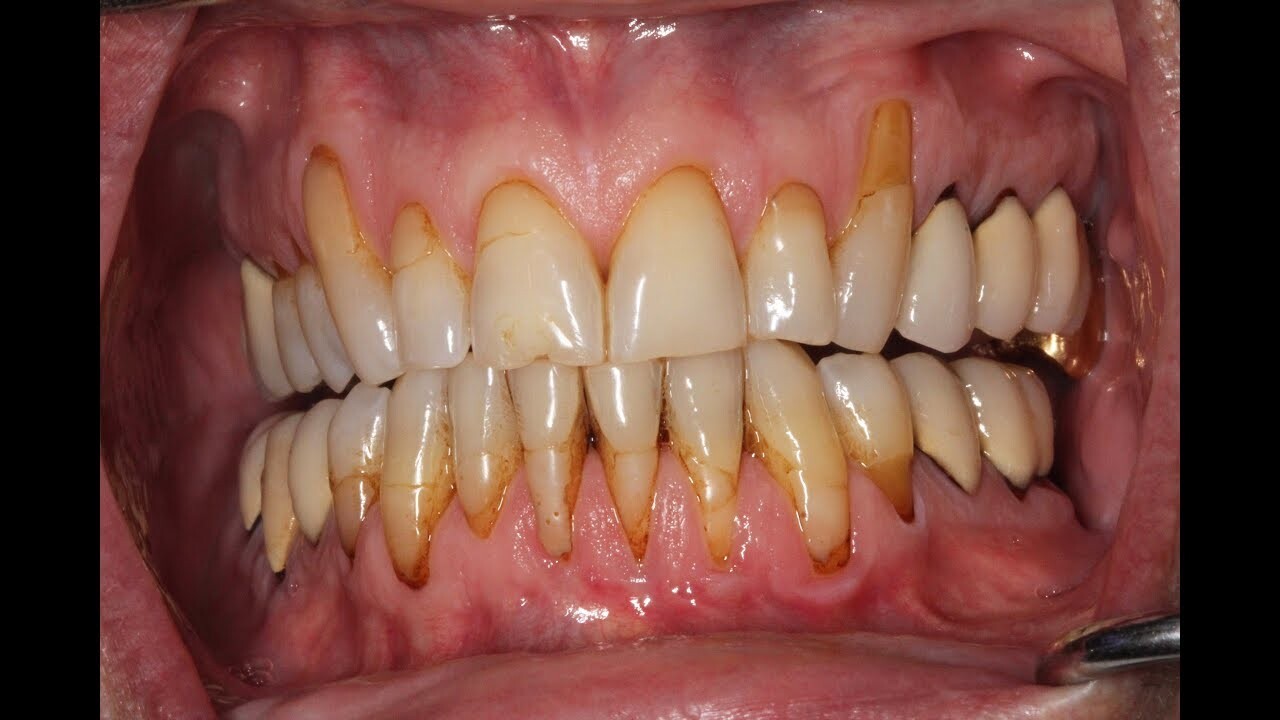

Yes, dentists can tell if you vape by looking for signs of it in the mouth. These include dryness or inflammation of the gums, discoloration, and a burning sensation when oral tissues are touched or probed. Additionally, the chemicals found in e-cigarette liquids will leave a specific residue on surfaces like teeth and tongue that can be observed during an examination and on the inside of your cheeks and lips. Additionally, if you vape too often, there may also be a noticeable discolouration in the teeth which will give away that you are a regular vaper. However, even if these signs are present it does not necessarily mean that you have gum disease. It is important to continue to practice good oral hygiene and seek regular check-ups with your dentist to ensure that any issues are caught as early as possible.

Can vaping cause receding gums?

Yes, vaping can lead to receding gums due to the toxic chemicals found in e-cigarette liquids. Every puff of a vape pen contains 700 toxins, several of which are known carcinogens and can lead to disease when inhaled. While the long-term consequences of vaping have yet to be studied, it is essential to note that people who also vape generally face higher risks than non-smokers for multiple types of cancer, gum infections and receding gums. Educating oneself on the potential risks and benefits associated with vaping will better ensure one’s well-being in the long run.